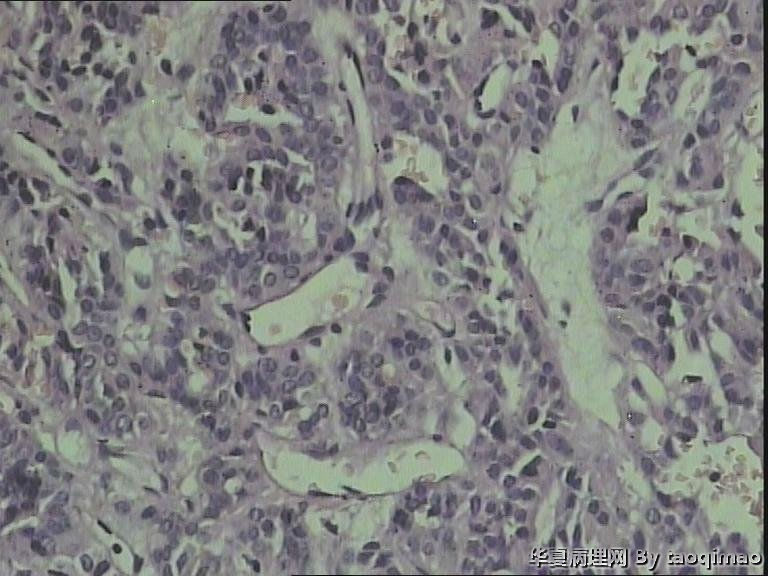

女 49岁,腰部及右下肢麻木坠胀1月

术中在椎管内,拨开马尾神经,可见椎体后缘约2*1cm实性肿物,与马尾神经粘连,边界清晰。

肉眼:红褐色不规则组织一块,2.5*1cm。剖面暗红兼灰白质软。

考虑粘液乳头型室管膜瘤。好发部位为圆锥和终丝

1、瘤细胞低柱状或立方形,大小形态较一致,围绕血管形成乳头状或假菊形团样,部分胞浆突起形成明显的无核区。

2、脊髓是室管膜的好发部位,经常会有相应的运动和感觉神经障碍。

3、鉴别:脉络丛乳头状瘤。免疫组化:室管膜瘤 CK(-),EMA(+),GFAP(+);而脉络丛乳头状瘤CK(+),GFAP(-).

粘液乳头型室管膜瘤。此病人发病部位特殊(马尾),组织学(乳头+粘液)也非常典型,是个很好的病例,可以作为教学片了,明确诊断应该没问题。

本病本质上为生长缓慢的胶质瘤(WHO I级)。免疫组化:GFAP(+),S-100(+),Vim(+),CK(-)。

From your description, the first choice should be myxopapillary ependymoma.

片中可以看见假菊形团结构,结合部位,应该是室管膜瘤。学习了。

If you have GFAP, you may do it but the diagnosis should be based on H&E stained slides, and this is a WHO grade 1 myxopapillary ependymoma.

各位老师不好意思,忘记把u盘拿回来了,今天做了5项免疫组化,CgA(+),S-100(+),CD34(-),EMA(-),Ki-67(-)。请各位老师进一步指教,我们没有CK,所以做的EMA。